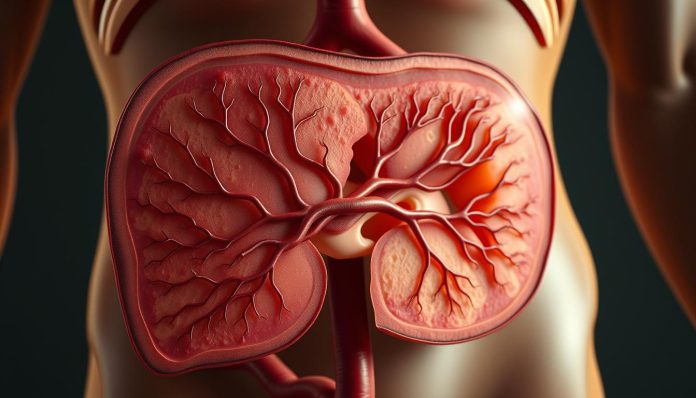

نظرة عامة على الكبد وموقعه في الجسم

الكبد هو أحد الأعضاء الأساسية في جسم الإنسان. يلعب دورًا كبيرًا في عمليات الحياة. يقع الكبد في الجزء العلوي الأيمن من البطن، تحت الحجاب الحاجز.

الموقع التشريحي للكبد

الكبد يقع في موقع استراتيجي في الجسم. يقع أسفل الضلوع في الجانب الأيمن من البطن. يمتد من أعلى البطن حتى منتصفها، محاطًا بأنسجة حماية.

التروية الدموية للكبد

الكبد يتلقى الدم من مصدرين رئيسيين. الوريد البابي يوفر 75% من الدم. الشريان الكبدي يوفر 25% من الدم. الدم يتصريف عبر الأوردة الكبدية إلى الوريد الأجوف السفلي.

التشريح المجهري والتركيب الداخلي للكبد

الكبد هو عضو معقد بتركيب مجهري دقيق. الفصيص الكبدي هو هيكل سداسي الشكل يظهر جمال التنظيم.